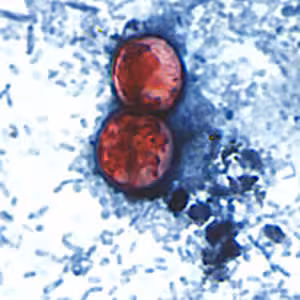

Cyclospora cayetanensis oocysts in wet mounts.

- Stained smears (using modified acid-fast stain or a modified safranin stain). Both modified acid-fast stains and modified safranin staining will stain Cyclospora cysts from a pink to brilliant red. Staining may be more variable using modified acid-fast.